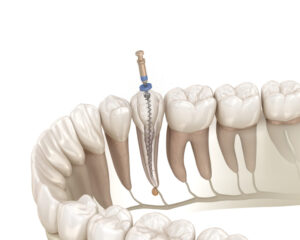

根管治療

湾曲していたり、分岐していたりと、根管の形態は非常に複雑です。

このような根管治療の場合、レントゲンでは一方向からの画像しか得られないため、根管の立体的な形態を把握することは困難です。

歯科用CT検査を行うことで、根管の数、形態、走行を三次元的に観察することができ、見落としがちな根管を発見したり、湾曲の程度を詳細に評価したりすることができます。